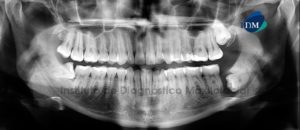

Paciente masculino de 20 años acude al Instituto de Diagnóstico Maxilofacial para evaluación imagenológica a nivel maxilofacial. A la evaluación de la radiografía panorámica se